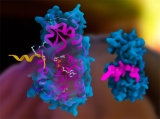

El dominioma humano revela la causa raíz de las enfermedades hereditarias

Investigadores del Instituto Wellcome Sanger y el CRG de Barcelona descubrieron que la inestabilidad proteica es uno de los principales impulsores de la formación de cataratas hereditarias y contribuye en algunas enfermedades neurológicas, del desarrollo y musculares.